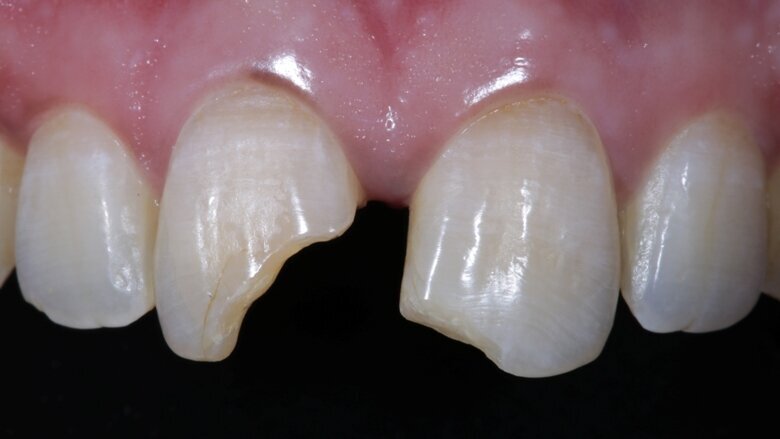

In the following case, two mal-aligned, fractured, non-vital central incisors were treated endodontically, bleached and restored using direct composite restorations.

The two maxillary central incisors were fractured and non-vital with noticeable darkening of shade [ Fig 1,2 ]. They were mal-aligned buccolingually and there was a midline diastema as well . There was no tenderness on percussion. There were peri-apical lesions associated with both incisors in the radiograph.

Non-surgical endodontic treatment was done in the 1st week. After the symptoms resolved completely we were ready to restore form, function and aesthetics. Non-vital in-office bleaching was done. Pola office bleach was used for the same, 3 cycles of 8 minutes each. It appeared that the shade had corrected completely after bleaching but we waited for it to stabilize.

Two weeks later, the shade [ Fig 3 ] stabilized and the teeth were ready for bonding. We observed that the central incisors were still darker than the neighboring teeth. Direct composite veneers were planned with the help of a lab made wax up [ Fig 4 ] and a putty index. Bevels were placed and most of the preparation was in enamel. After the total etch protocol, 5th generation bonding agent was used. 3M Z350XT shades were used for the build up. A2 Enamel shade was used for the palatal shell [ Fig 6 ] and the proximal walls [ Fig 11 ].